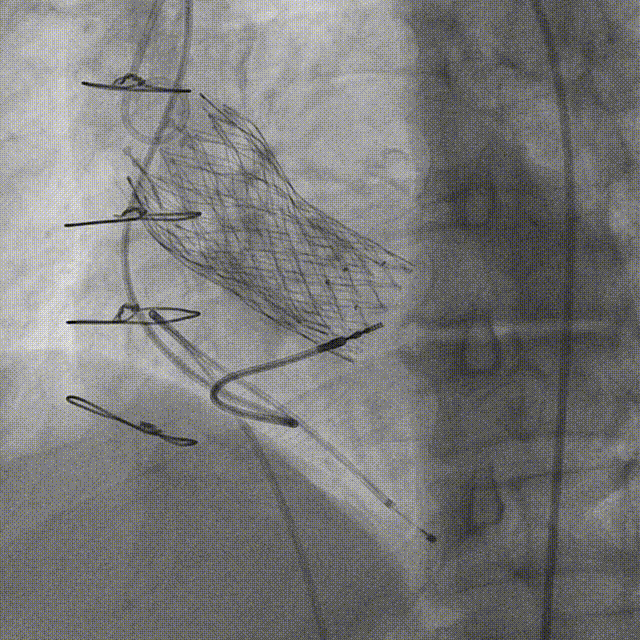

TAVR操作全过程

2.TAVR术后冠脉造影:

3.经左股动脉角度猪尾行主动脉根部造影。

4.猪尾直接跨瓣并进行左室测压。